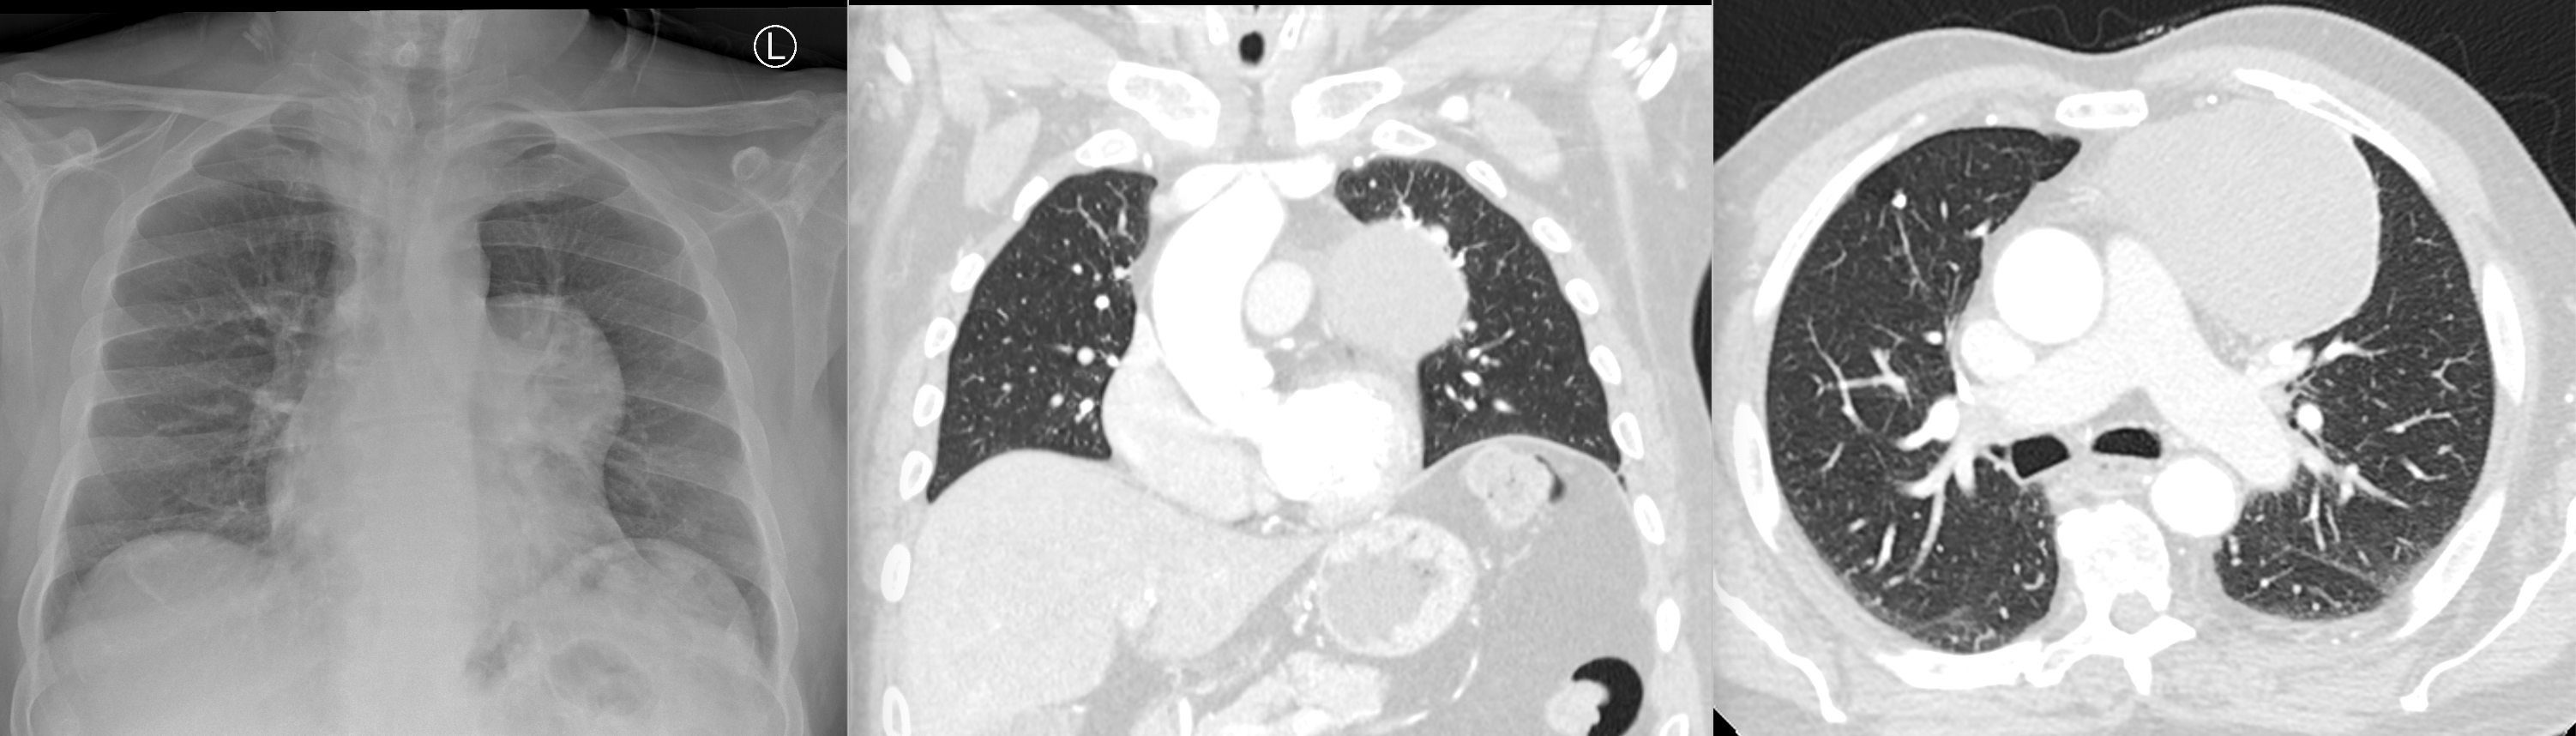

Hilum overlay sign - anterior mediastinal mass